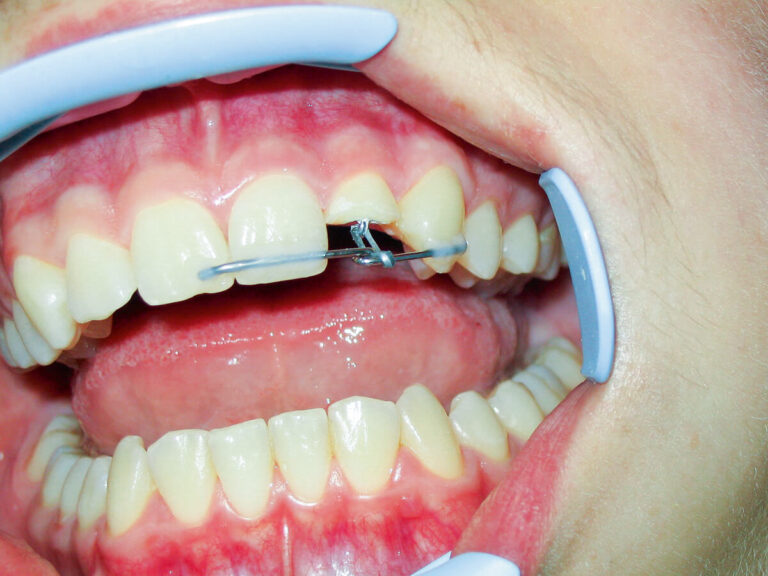

Czym jest elektrokoagulacja? Elektrokoagulacja to zabieg polegający na kontrolowanym wykorzystaniu prądu elektrycznego w celu zamknięcia naczyń krwionośnych oraz usunięcia zmienionych tkanek. W stomatologii metoda ta znajduje zastosowanie przede wszystkim w chirurgii i periodontologii. Stomatolog w nowoczesnej klinika stomatologiczna Kraków wykorzystuje…